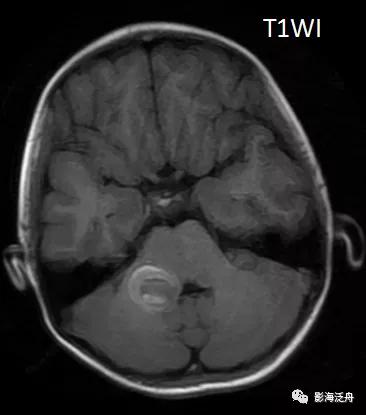

话不多说,上病例:患者女,12岁,头晕、头痛伴呕吐一天,无发热,无咳嗽,入院后行MR平扫检查,如下图↓↓

上图可见右侧桥臂一类圆形异常信号,T1WI呈中央稍低信号,边缘环形高信号,T2WI以低信号为主,局部可见液液分层(红箭),高、低b值DWI显示病变区域信号丢失。通过上述信号改变,不难看出是一个急性期血肿(血肿分期详见 MR上脑出血信号的演变机制)。